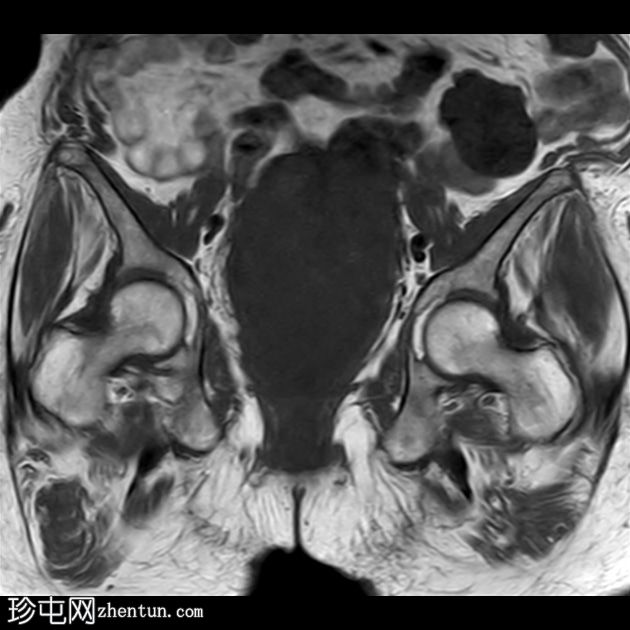

冠状位

T1

15.jpg

子宫呈U形,宫底轮廓消失,宫底突出至扩张的阴道内,宫颈位于内翻的宫底上方(II级子宫内翻):

左侧附件复合体病变,包含实性和囊性成分,轴向径约为 5.3 x 4.7 cm。实性成分 T1 加权像呈低信号,T2 加权像呈中信号,伴有扩散受限和增强。

检查结果显示为 II 级子宫内翻,子宫底可见一巨大肿瘤性实性肿块,该肿块延伸并扩张了阴道,具体情况如上所述。

左侧附件复杂肿瘤性病变。